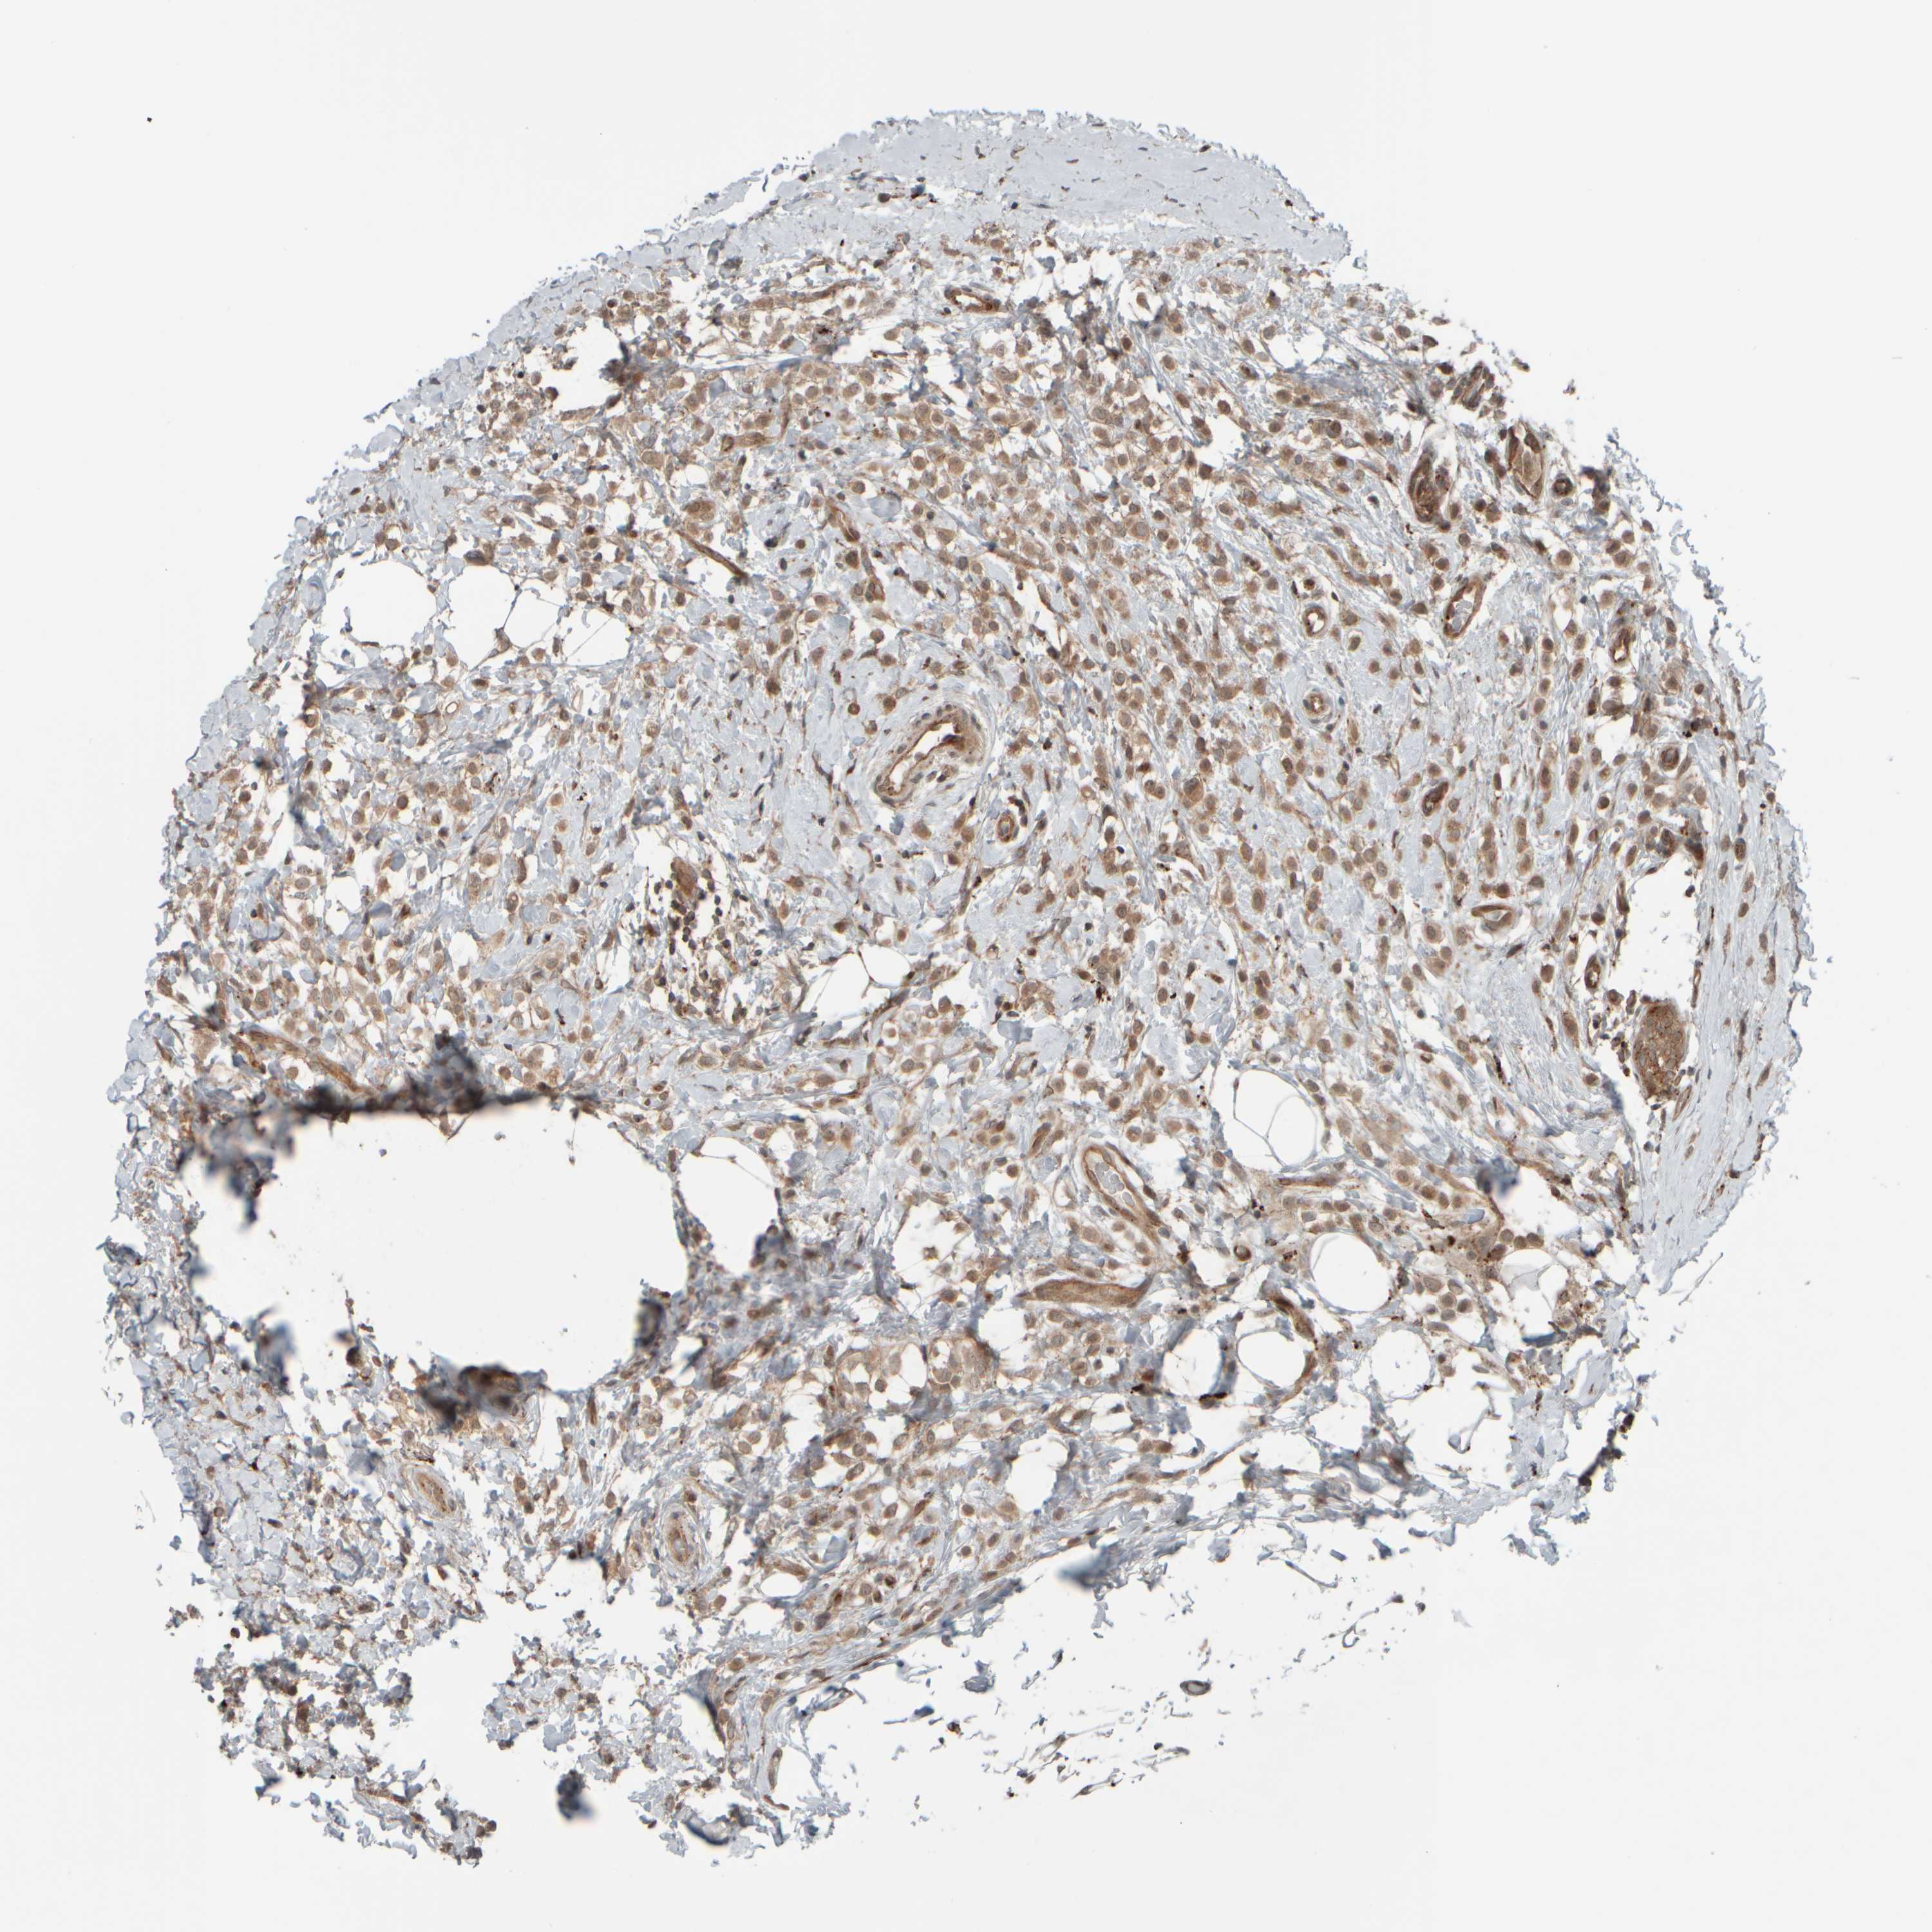

CANCER BREAST CANCER Show tissue menu

BRCA TCGA BRCA VALIDATION PROTEIN EXPRESSION